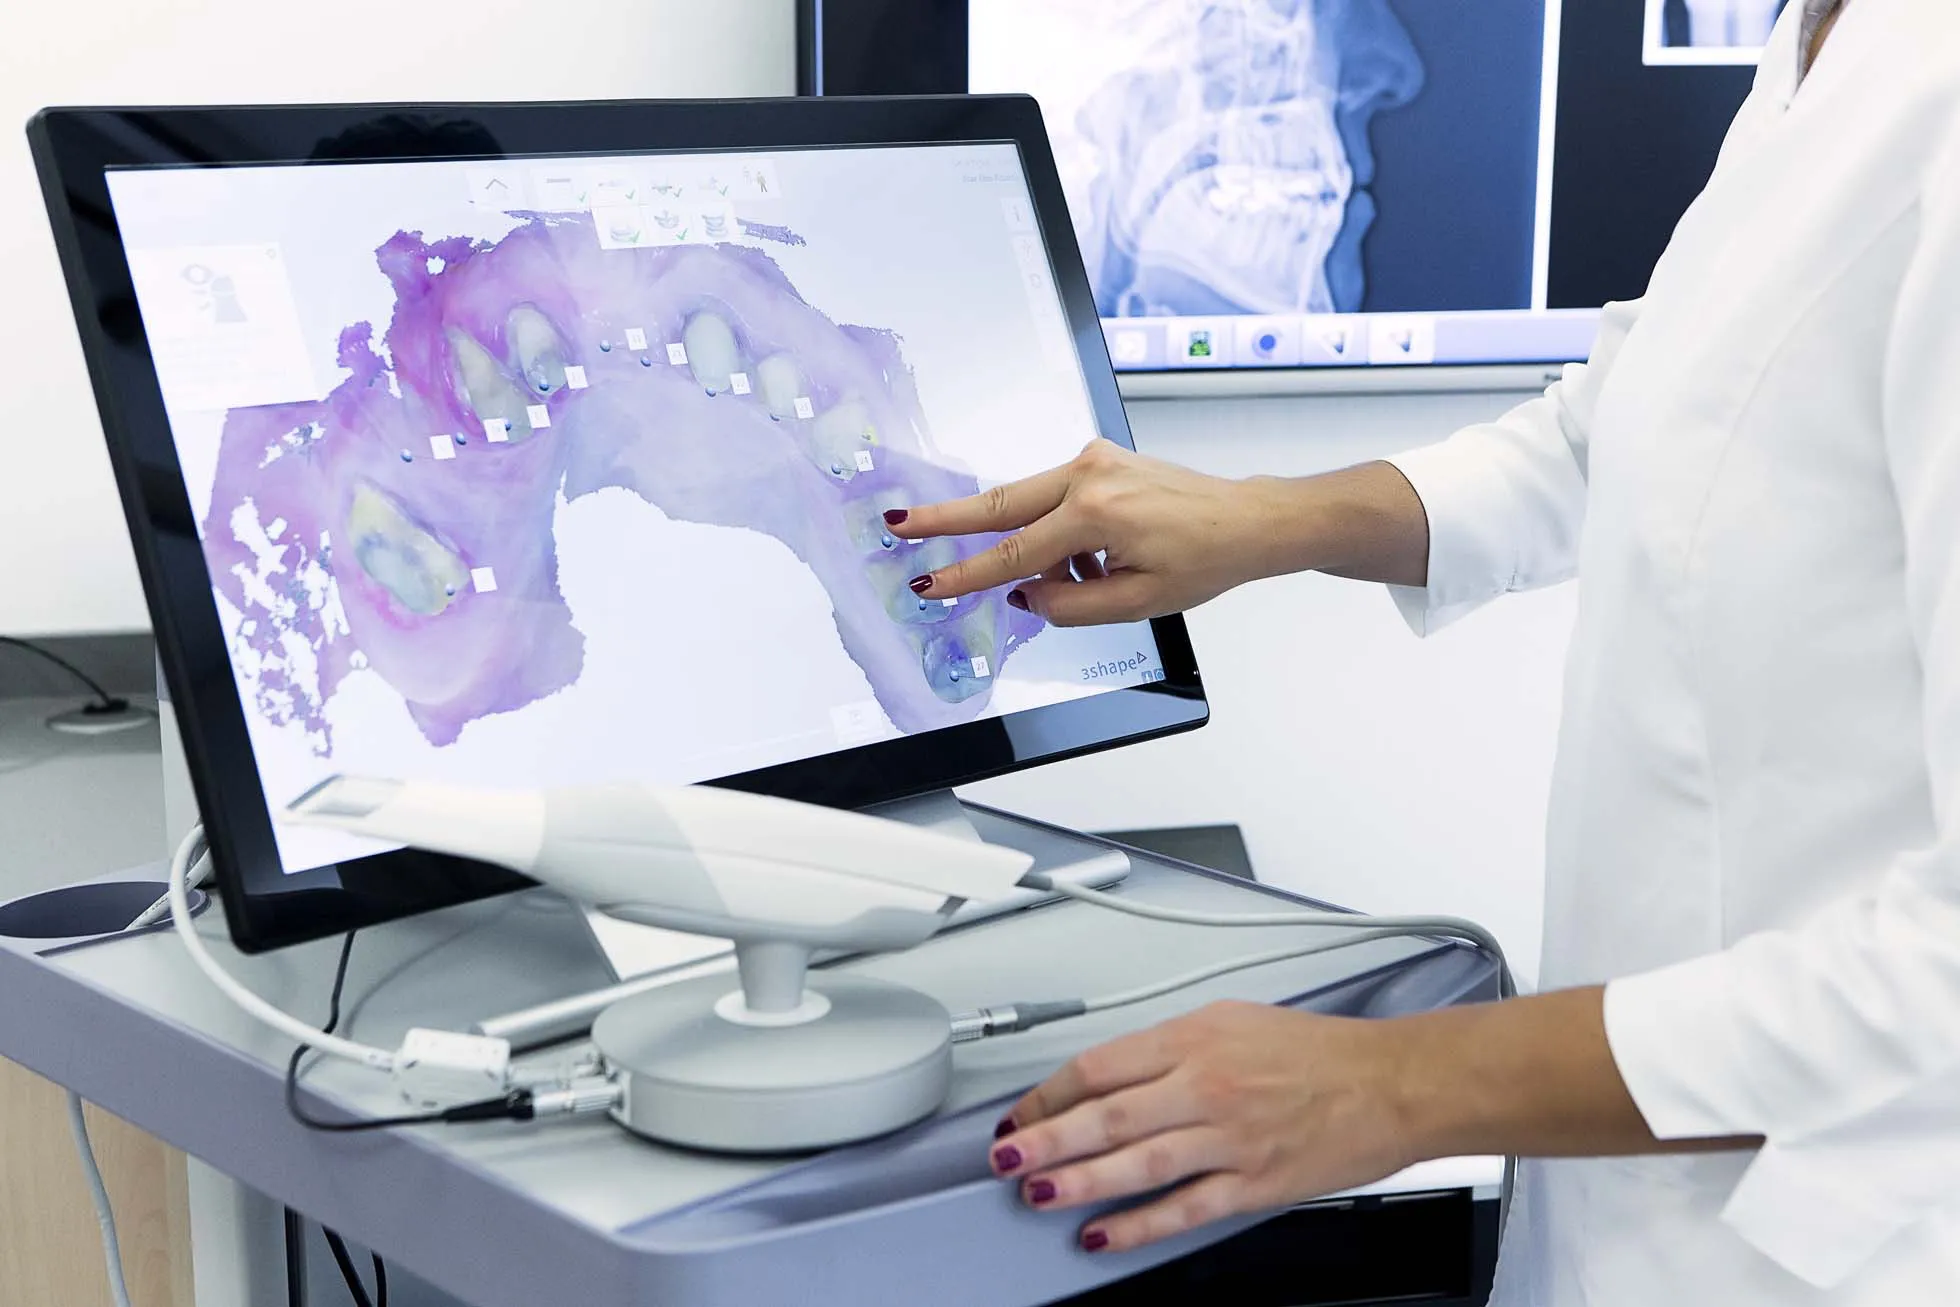

Digital Precision

Where Technology Meets Comfort

Step into our state-of-the-art clinic, where professional-grade digital dentistry delivers affordable same-day crowns and advanced imaging, transforms your dental experience. Imagine: Precise, efficient, and comfortable treatments, designed to save you time and ease your worries.

Experience Dental Innovation with Digital Precision

At Gallery Dental, we’re revolutionizing dental care with advanced technology like same-day crowns, high-definition digital X-rays, and gentle laser dentistry. Experience the difference: Faster, more efficient, and minimally invasive procedures, designed for your comfort and peace of mind.

Digital Dentistry